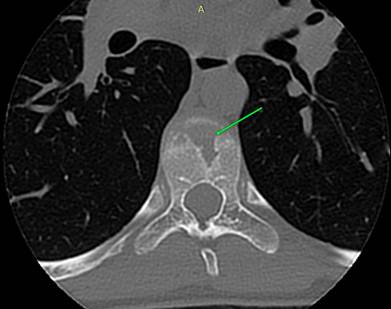

РК

– томография грудного отдела позвоночника того же ребенка, саггитальный скан,

который эквивалентен предыдущей рентгенограмме.

Хорошо видны хрящевые узлы различного размера, вдающиеся в тела

позвонков. Вокруг узлов заметно избыточное костеобразование – склероз

замыкательных пласитнок. Апофизарные кольца видны в виде точек повышенной

костной плотности у переднего и заднего краев тела позвонка, их изображение на

саггитальном скане не несет диагностической информации.

Аксиальный скан, виден крупный хрящевой узел в теле

позвонка (зеленая стрелка)